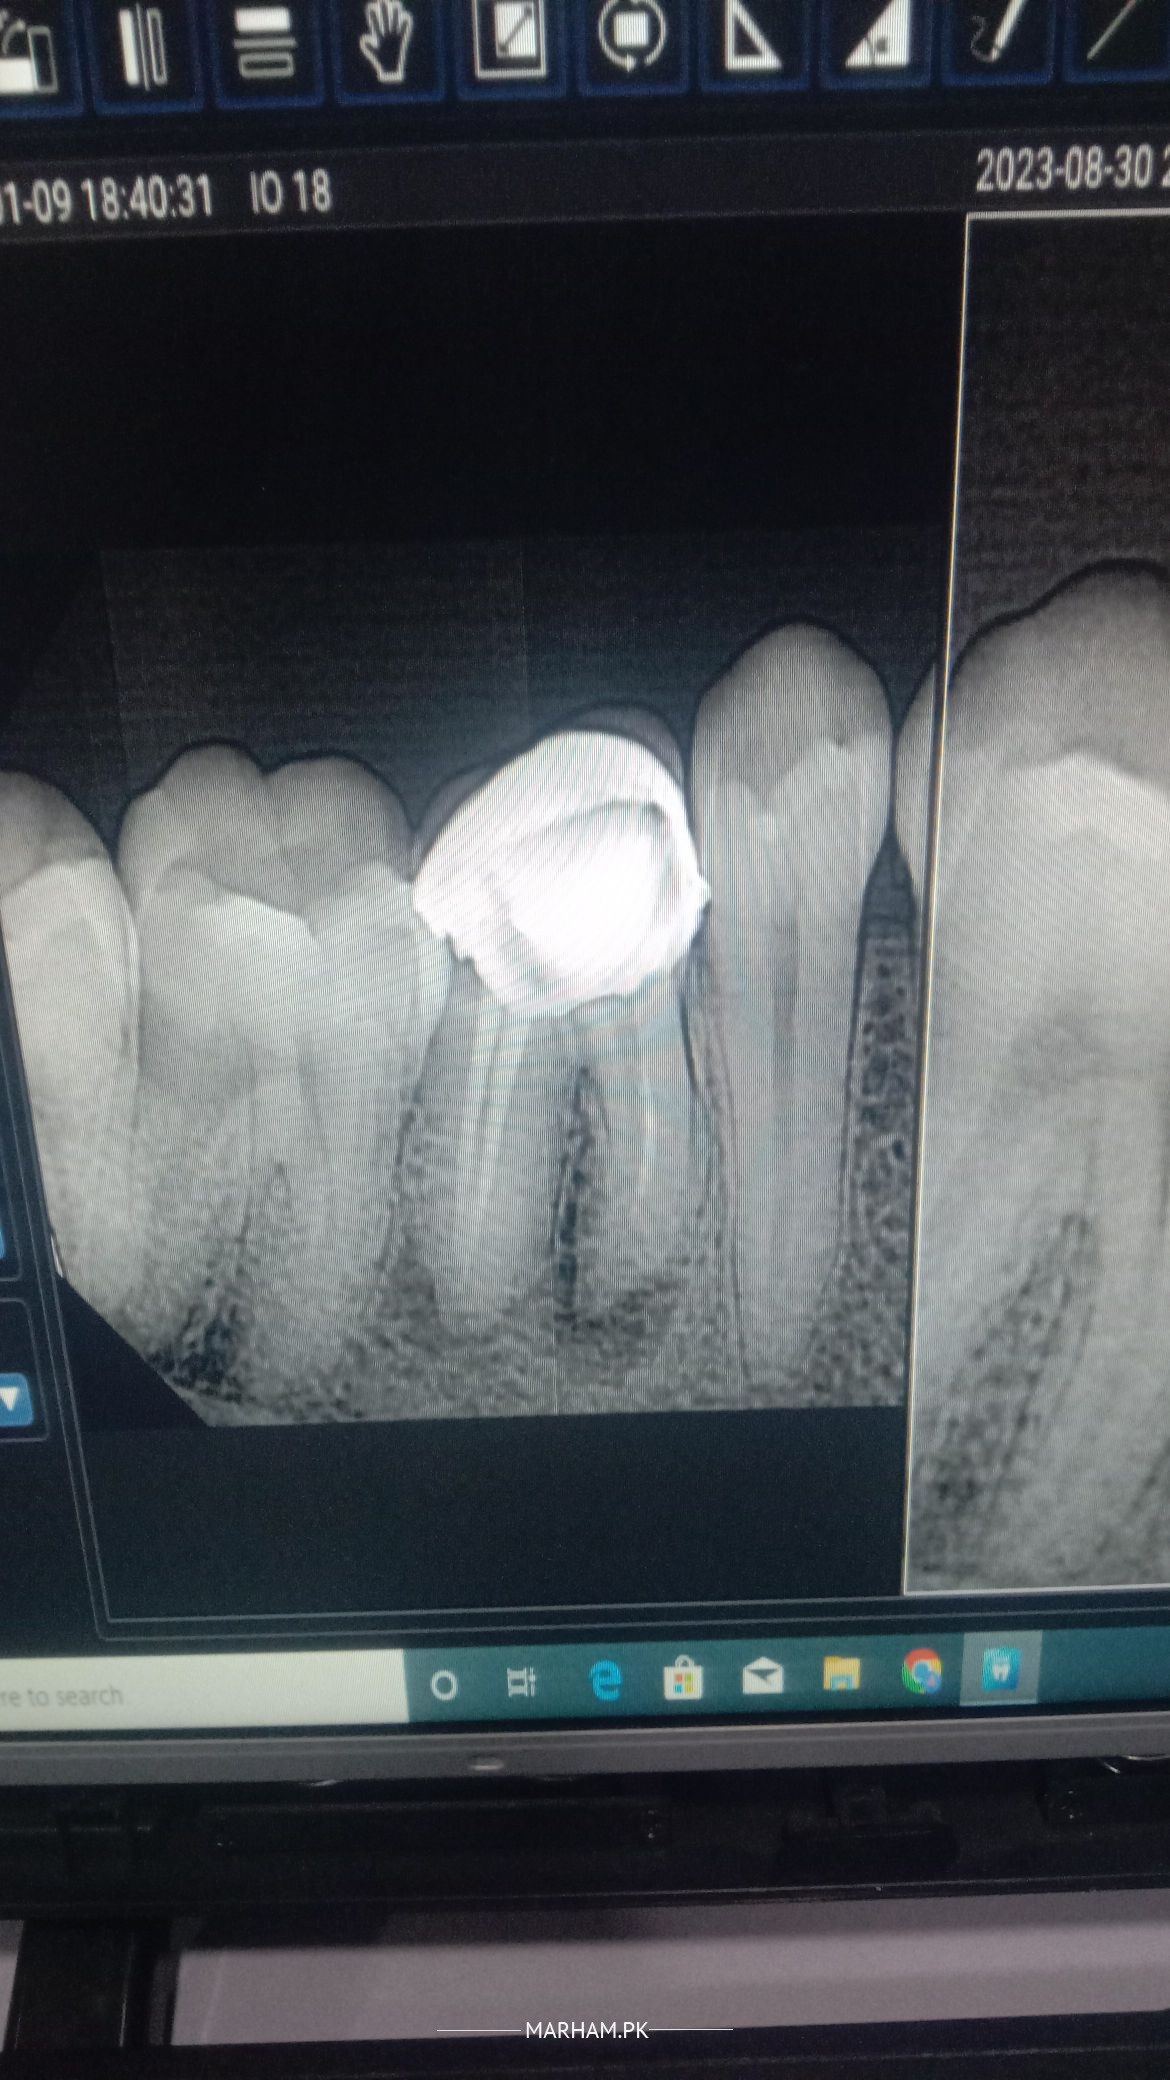

Aoa rct on this teeth was performed 2 months ago . Still seems minor infection. It will resolved by it's own or should i take any antibiotics?

Rct is not done properly. Thats why infection might persist. Otherwise any translucency on radiograph takes at least 6 months to disappear.

I can’t see the picture. But presence of infection is not good. It should be treated. If the dentist has used medication while sealing your RCT, we can hope it will resolve

if there is no pain dont worry in case of pain re rct should be done